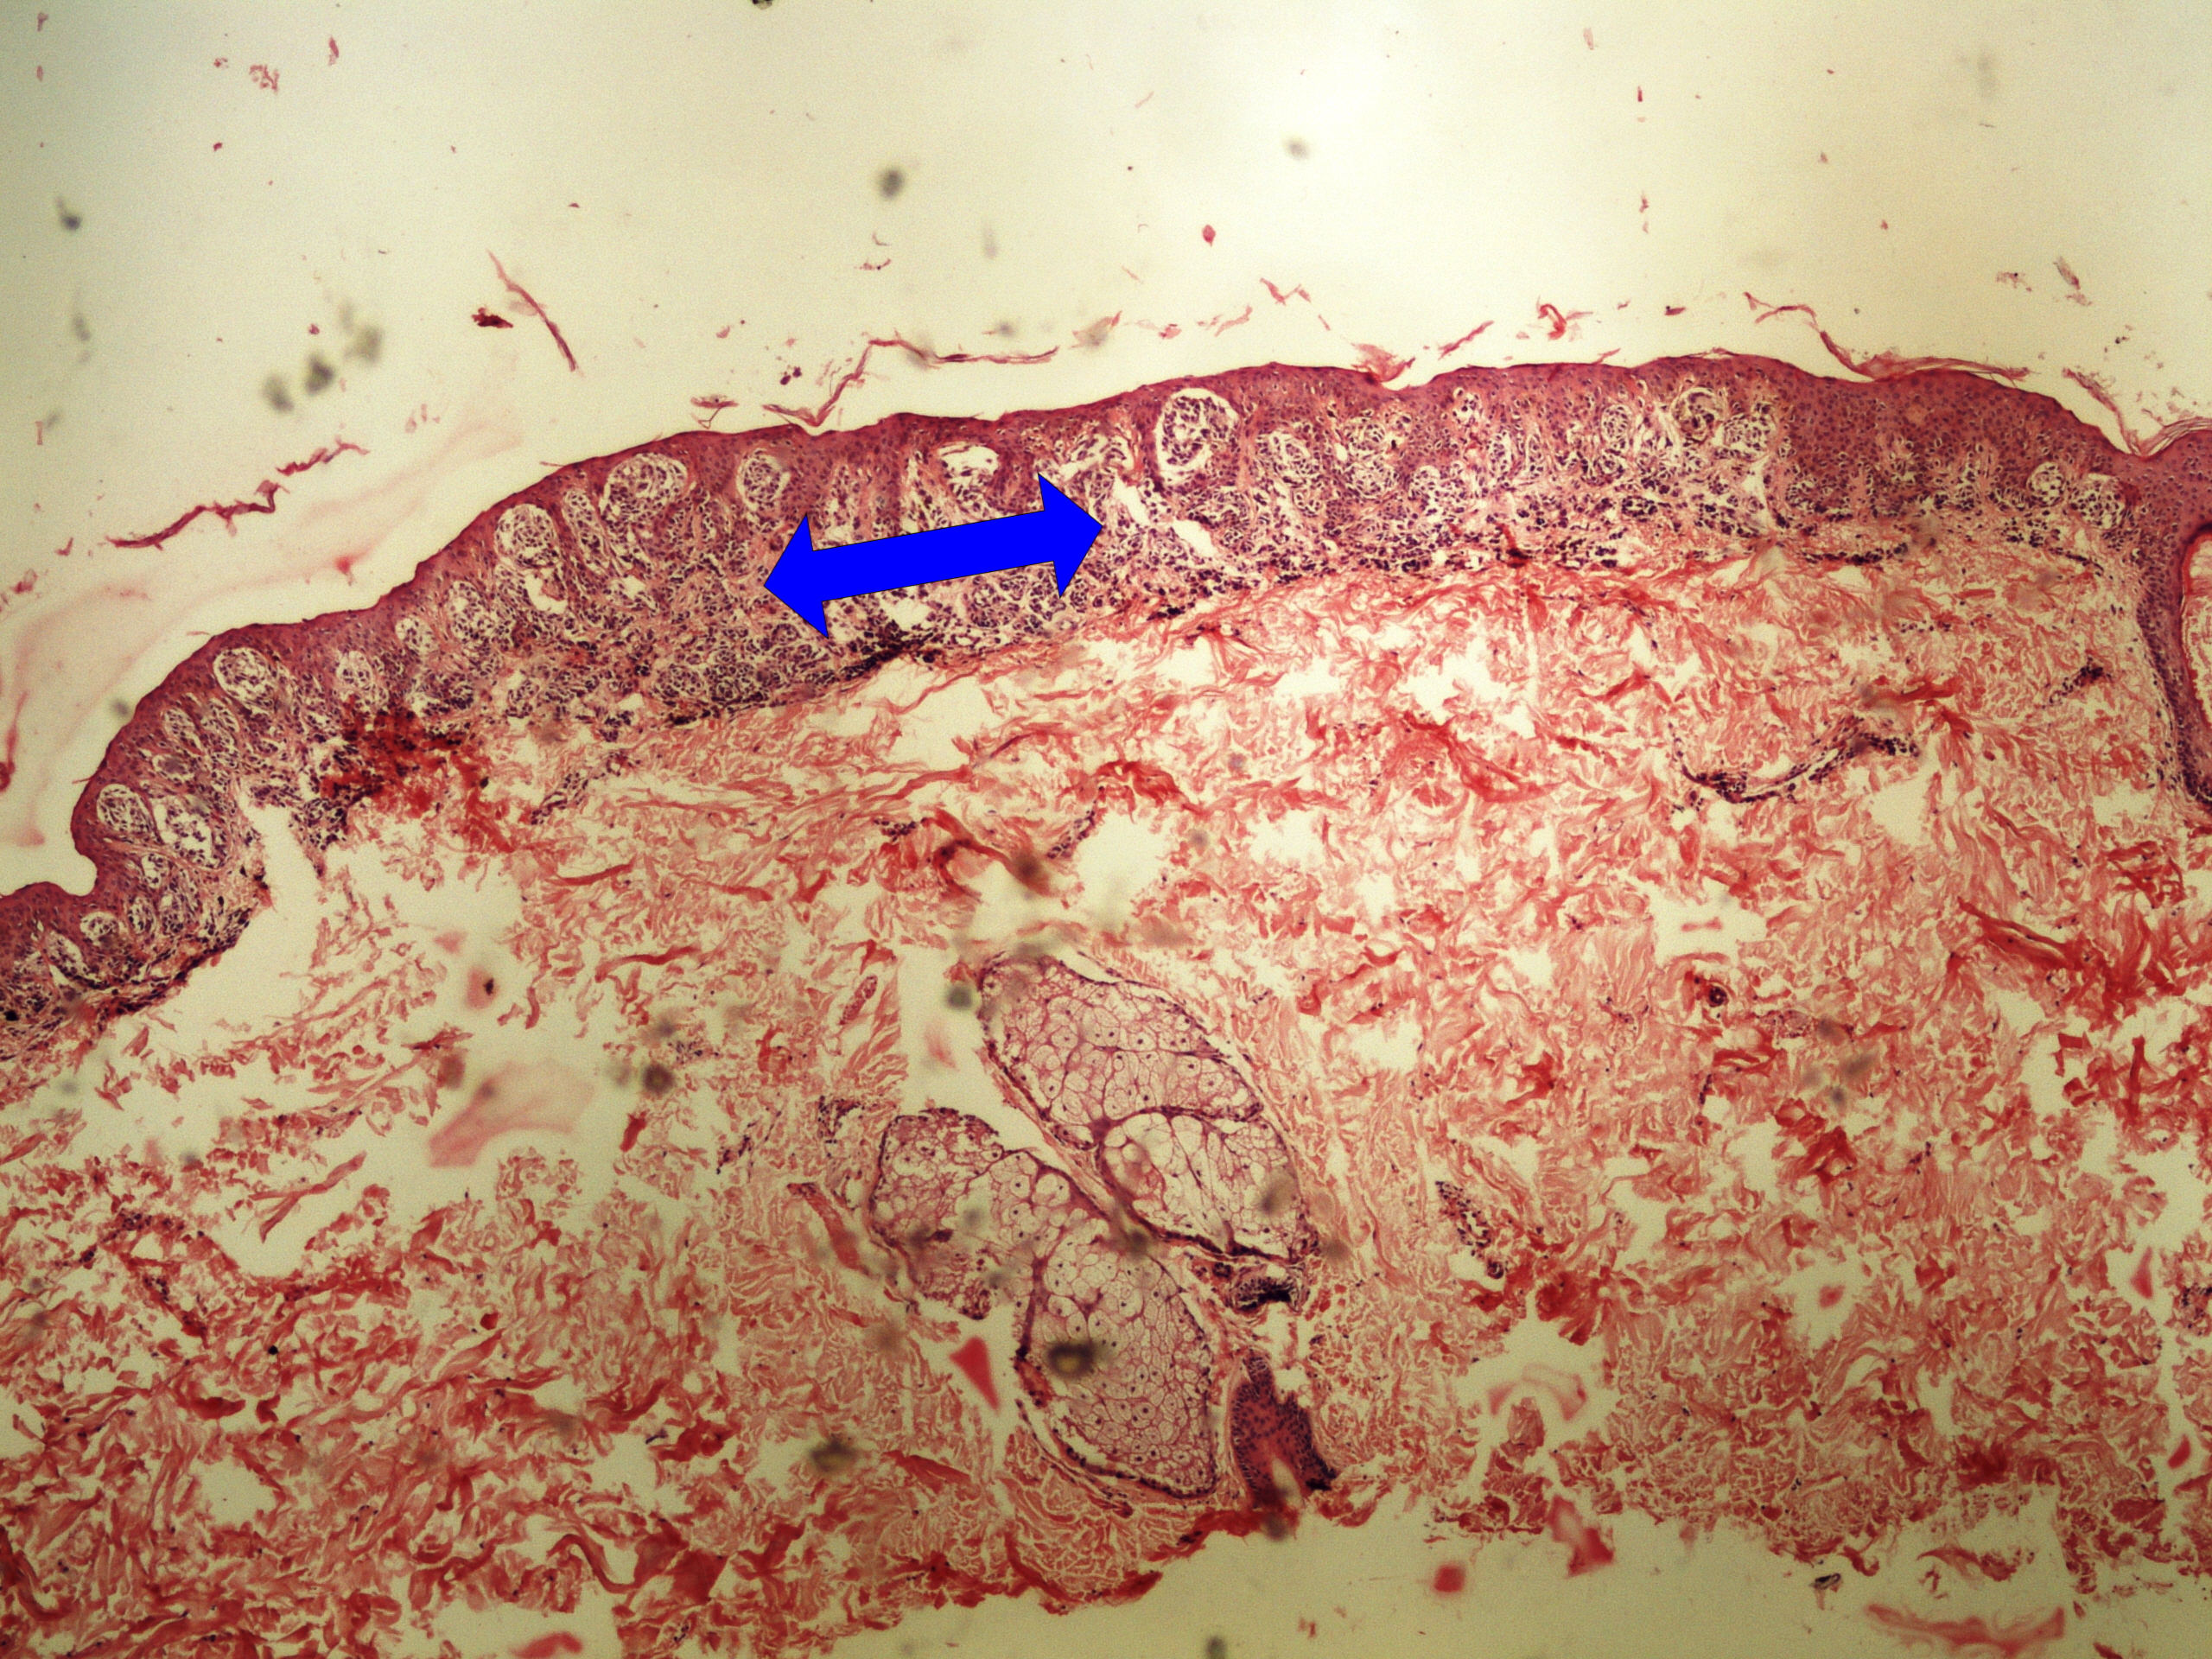

Preparát č.7 a č.8 – koetánní teratom ovaria

Struktury

- chrupavka

- tuková tkáň

- sebaceózní žlázka

- potní žláza

- epitel